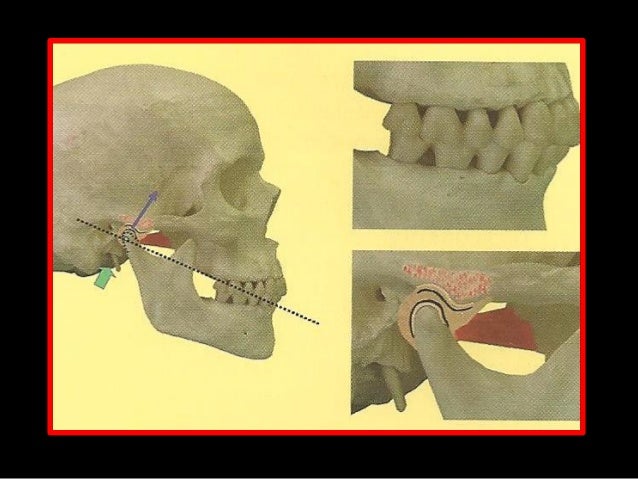

5. 5. Relação Cêntrica “É uma posição crâniomandibular onde o côndilo e disco estão firmemente alojados na posição na posição mais anterior e superior da cavidade glenóide, fixados por ligamentos e músculos; praticamente imutável, fisiológica, reproduzível, ponto de partida para exame de diagnóstico e tratamento restaurador e de problemas oclusais, não dependendo de dentes e contatos dentários...” MEZZOMO, E., 2008

6. 6. Relação Cêntrica “É uma posição estritamente relacionada à posição condilar, não apresentando nenhuma relação com os contatos dentários.” PEGORARO, et. al.; 2002